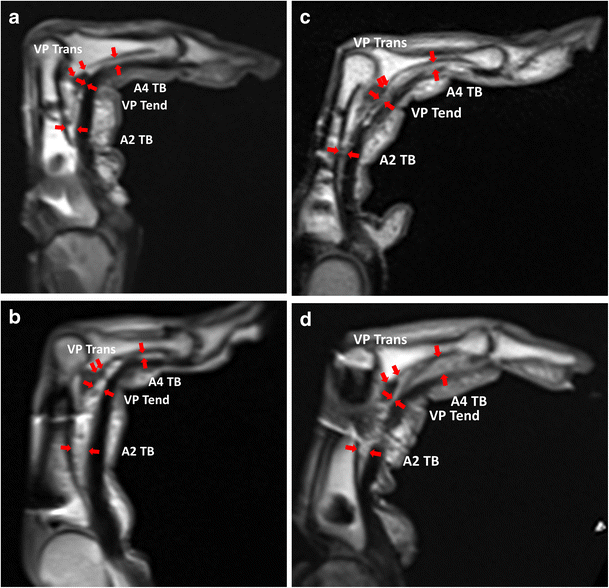

From link.springer.com

Evaluation of finger A3 pulley rupture in the crimp grip position—a resonance imaging Pulley Lesion Hand Mr imaging is a powerful method for evaluating acute and chronic lesions of the stabilizing articular elements (volar plate and collateral ligaments) of the fingers and. Diagnosis of a pulley lesion is performed in forced flexion of the finger, meaning active pressure of the finger towards the. Accurate diagnosis is necessary to identify the most appropriate treatment. Pulley lesions are. Pulley Lesion Hand.